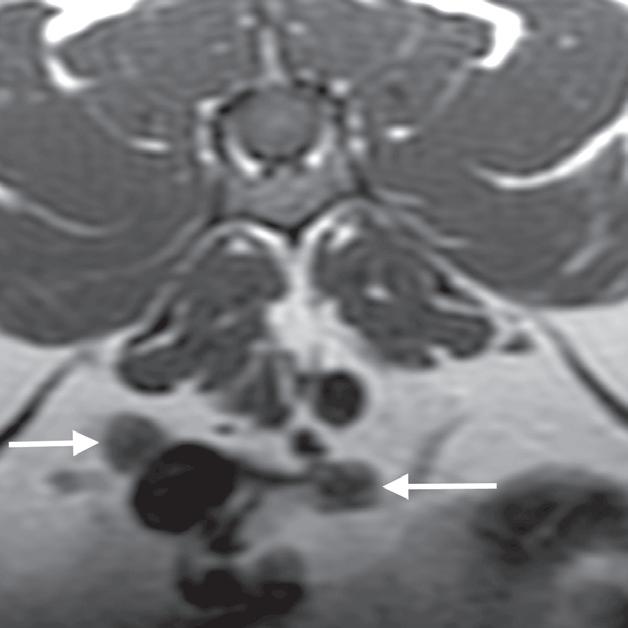

Rycina 5.6.6. Przysadkowozależna nadczynność kory nadnerczy (pies) TK

Badanie wykonano u 12-letniego, kastrowanego boston teriera z podejrzeniem przysadkowozależnej nadczynności kory nadnerczy. W badaniu natywnym oba nadnercza (a, b – strzałki) są powiększone i zaokrąglone, a także wykazują jednorodną densyjność tkanek miękkich. Widoczna jest mineralizacja ściany tętnicy krezkowej przedniej, która jest zmianą wtórną do zespołu Cushinga (b – gwiazdka). Obraz po podaniu dożylnego środka kontrastowego mózgowia ujawnia duży, intensywnie wzmacniający się rozrost przysadki (d – otwarta strzałka), przypuszczalnie o charakterze funkcjonalnym